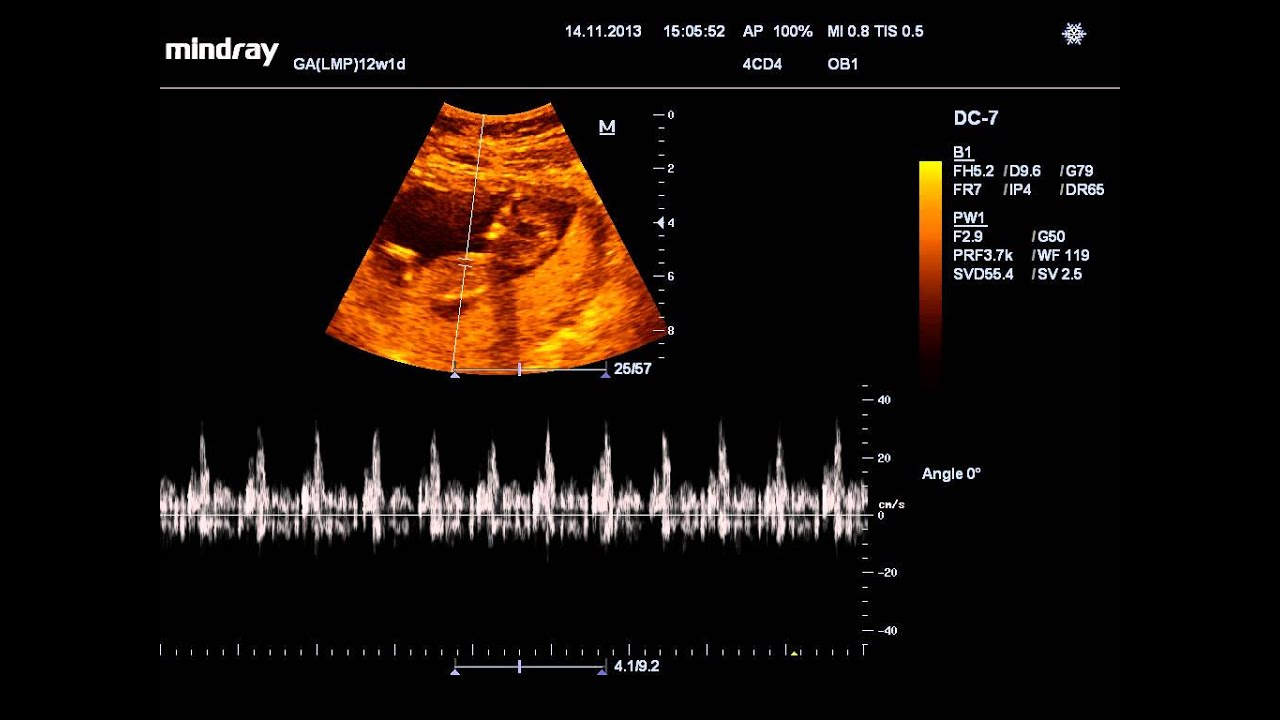

Методы выслушивания сердцебиения плода

С помощью УЗИ можно не только услышать сердце ребенка, но и посмотреть, в каком состоянии находится плацента, какие размеры имеет плод и т. д

Это еще один метод выслушивания сердцебиений ребенка. Актуален метод для 18-й – 28-й недели гестации, если врач подозревает, что сердце ребенка формируется не совсем правильно. Эхокардиография показывает строение сердца и кровотока.